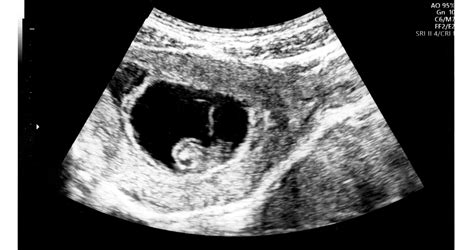

A 35 hetes terhesség a harmadik trimeszter, a 8. hónap vége felé jár. Ez azt jelenti, hogy ha minden a tervek szerint halad, mindössze öt hét múlva megszületik az új családtag. A 35 hetes magzat már több, mint 2,5 kg súlyú és 45-46 cm hosszú. Bár a szervek növekedésének többsége ekkorra befejeződik, a tüdő, az agy és a máj az utolsó hetekben válnak teljesen éretté. Az agy a 35. és a 39. hét között még harmadával nő, a pici pedig erős súlygyarapodásba kezd, hetente körülbelül 25-35 dkg-ot hízik, ami szükséges ahhoz, hogy születés után tartani tudja a testhőjét.

A 35. hét betöltésével, amennyiben minden a tervek szerint halad, mindössze öt hét múlva megszületik az új családtag. Noha a 35. hétre a magzat fejlődésének többsége befejeződik, a tüdő, az agy és a máj az utolsó hetekben válnak teljesen éretté.